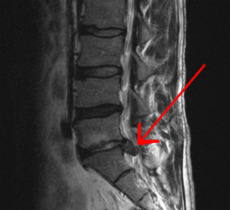

Herniated lumbar disc

Lumbar disc herniations occur in the back, most often between the fourth and fifth lumbar vertebral bodies or between the fifth and the sacrum. Here, symptoms can be felt in the lower back, buttocks, thigh, anal/genital region (via the perineal nerve), and may radiate into the foot and/or toe. The sciatic nerve is the most commonly affected nerve, causing symptoms of sciatica. The femoral nerve can also be affected and cause the patient to experience a numb, tingling feeling throughout one or both legs and even feet or a burning feeling in the hips and legs.[20] A herniation in the lumbar region often compresses the nerve root exiting at the level below the disc. Thus, a herniation of the L4–5 disc compresses the L5 nerve root, only if the herniation is posterolateral.